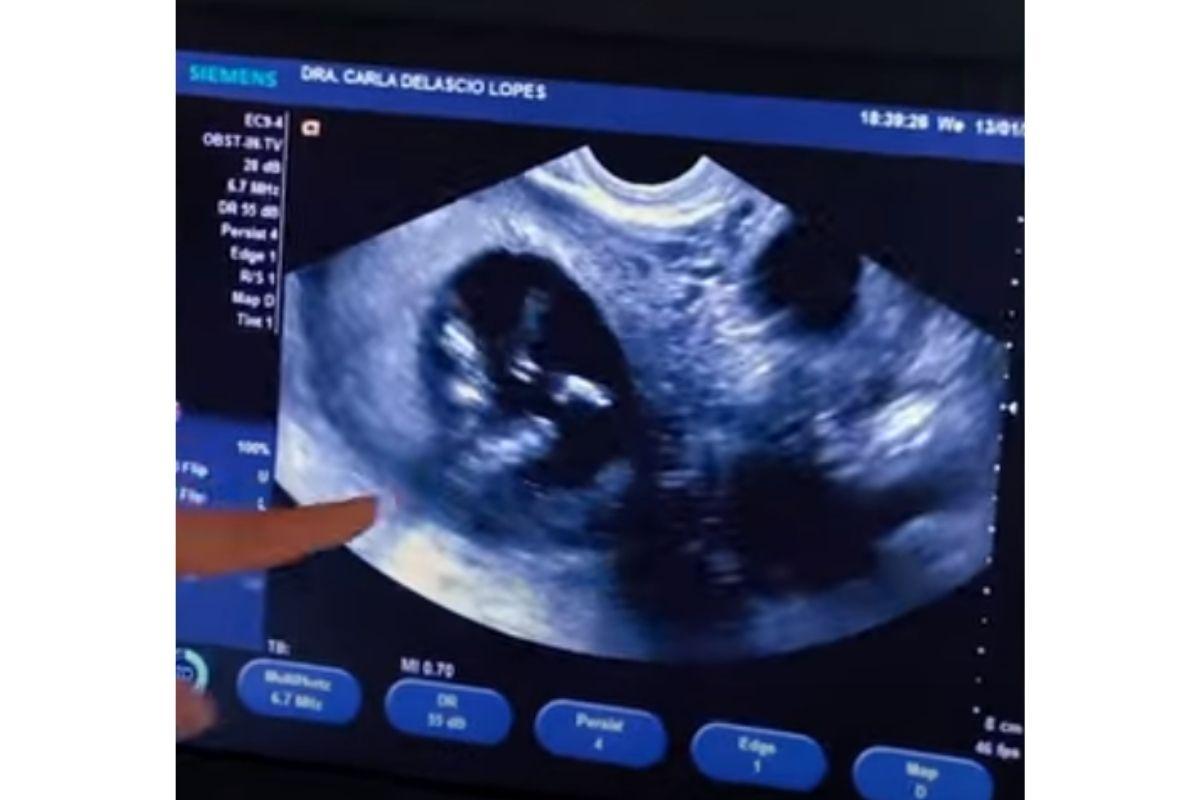

No vídeo, ela compartilhou diversas imagens emocionantes do ultrassom do bebê, além de momentos em que o parceiro acaricia e beija a barriga dela. A ex-BBB também aproveitou o vídeo para relembrar momentos da história do casal, que estão juntos há 4 anos, mas só se assumiram como casal no ano passado.

Bianca seguiu animada, contando sobre a evolução da gestação. “A gente foi em uma consulta com o obstetra hoje e a gente viu ele ou ela balançando”, disse, animada. Ela contou que o casal já conversava sobre a vontade de ter filhos. “Ele já queria ser pai, eu queria ser mãe”, contou. Os dois, porém, pensavam sobre possibilidades de serem mãe e pai solos, por medo de depender de um parceiro.